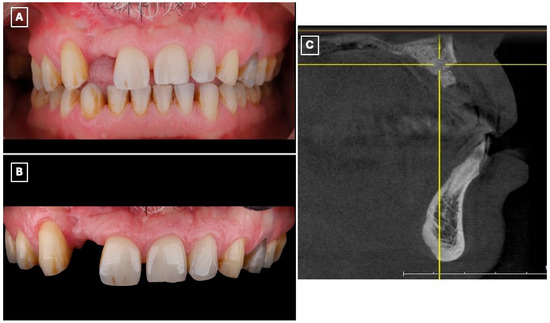

A 45-year-old male presented to the Prosthodontics Clinic at King Abdulaziz Medical City, Ministry of National Guard, Jeddah, Saudi Arabia, with a missing maxillary right lateral incisor (#12) and requested esthetic rehabilitation (Figure 1A,B). His chief complaint was: “I want my smile improved and the missing tooth replaced with a natural-looking option.” The patient reported no relevant medical conditions, and both medical and family histories were noncontributory.

Figure 1.

Preoperative clinical and radiographic assessment of the maxillary anterior region supporting treatment selection. (A) Frontal intraoral view demonstrating the missing maxillary right lateral incisor (#12), associated asymmetry of the anterior smile line, and localized esthetic disharmony within the maxillary anterior segment. (B) Closer intraoral view highlighting the edentulous space, favorable gingival architecture, and intact adjacent enamel surfaces, which are prerequisites for predictable enamel-bonded adhesive restorations. (C) Sagittal cone-beam computed tomography (CBCT) cross-sectional image of the lateral incisor region demonstrating limited residual alveolar ridge width and altered ridge contour following previous augmentation procedures. These findings, in conjunction with prior surgical outcomes and patient preference to avoid further intervention, supported the exclusion of implant therapy and the selection of a minimally invasive, non-surgical adhesive prosthodontic approach.

The patient had previously undergone multiple bone augmentation procedures in the periodontics department; however, despite these interventions, the residual alveolar ridge volume in the maxillary right lateral incisor region remained insufficient for predictable implant placement. This assessment was based on prior surgical outcomes, clinical ridge morphology, and interdisciplinary evaluation. Preoperative cone-beam computed tomography (CBCT) imaging (Figure 1C) demonstrated limited bucco-lingual ridge width and an unfavorable ridge contour at the lateral incisor site, further supporting the decision to exclude implant therapy.